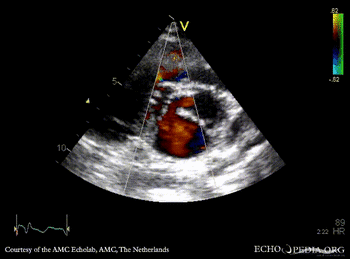

| Courtesy of: AMC Echolab, AMC, The Netherlands | |

| PLAX | PLAX: Color Doppler, ????? |